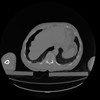

34 CUERPO,CE,Vol,1.0,CUERPO,,